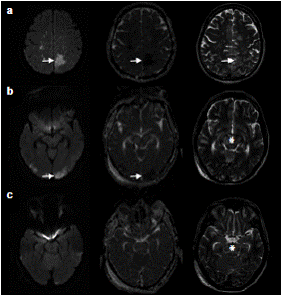

En la tomografía computadorizada de control se observó persistencia de la hipodensidad de la región mesencefálica, así como cambios por la craniectomía suboccipital y el drenaje del hematoma cerebeloso derecho (figura 2). Debido a la persistencia del deterioro clínico, se hizo una resonancia magnética en la cual se encontraron múltiples eventos isquémicos (edema citotóxico) que afectaban especialmente los territorios de ambas arterias cerebrales posteriores y de la arteria cerebral media, y el territorio limítrofe profundo de dichas arterias; la hipodensidad tomográfica en el mesencéfalo y en el puente correspondía a edema vasogénico (figura 3).

Se decidió tomar imágenes de las lesiones por resonancia magnética, en las cuales se evidenció un aumento de las zonas isquémicas en ambas arterias cerebrales posteriores y en la arteria cerebral media, así como en el territorio limítrofe profundo de esta, además de edema vasogénico que se extendía hasta la región del núcleo basal, la mesencefálica y el tallo cerebral, y la sustancia blanca profunda de los hemisferios cerebelosos (figura 4).

Lo anterior indica que las lesiones de este síndrome no son únicas y que, más bien, pueden encontrarse en forma combinada, como en el presente caso, en el cual el edema cerebral holohemisférico evolucionó de edema vasogénico a edema citotóxico con subsecuentes infartos cerebrales, aunque no en el tallo cerebral, en la región del núcleo basal ni en el mesencéfalo, en donde el compromiso correspondía al patrón profundo del síndrome (Deep Brain Reversible Encephalopathy, DBRE).

Según algunas publicaciones, la localización y la distribución del edema pueden determinar la gravedad de la lesión; con base en las imágenes por resonancia magnética de recuperación de inversión atenuada de fluido (Fluid-Attenuated Inversion Recovery, FLAIR), MacKinney, et al. 11, por ejemplo, definieron: los casos leves, como aquellos en los cuales el edema afecta la sustancia blanca cortical y subcortical; los casos moderados, como aquellos en los cuales existe edema confluente que se extiende desde la corteza hasta la sustancia blanca profunda, y los casos graves, como aquellos en los cuales se observa edema confluente que se extiende desde la corteza hasta el ventrículo, o edema o hemorragia, o desplazamiento de la línea media, o herniación, o efecto de masa, o compromiso del cerebelo o del tallo cerebral o los núcleos basales (DBRE). El presente caso se clasificó como grave, lo cual probablemente explica el comportamiento maligno y el desenlace fatal.